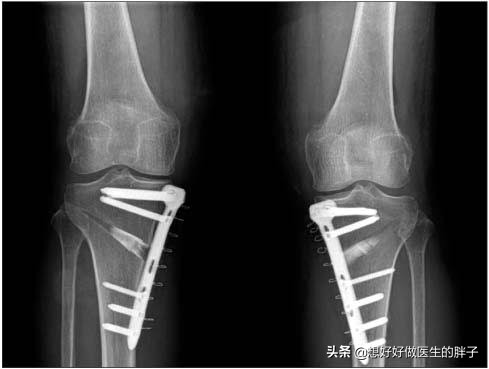

对于这个阶段的患者,我们往往建议进行关节手术治疗来解决问题了。可以选择的方式,每个人都不同,有一些患者可以根据病情不同,可以尝试保膝手术治疗,如高位胫骨截骨矫形,比如部分关节置换。

胫骨高位截骨HTO